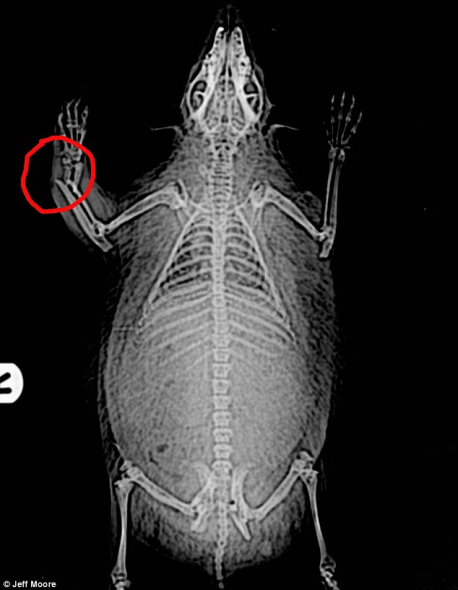

X光照片显示这只刺猬右边前腿骨折,完全康复将需要6周。